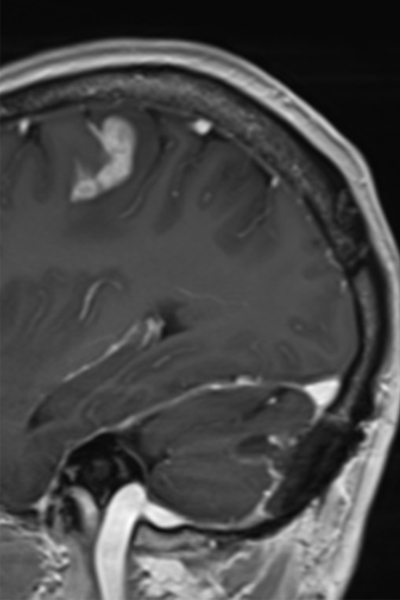

転移性脳腫瘍 治療経過の一例(手術+全脳放射線治療)

初診時

手術後

放射線治療後3ヶ月

○手術ができない大脳の病変

○手術が必要な小脳の病変